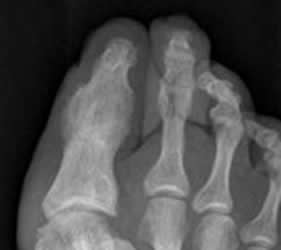

Fig 140. Artrosis.

Rx AP. Fractura intra-articular de la falange distal. Luego de su consolidación, deja como secuela la fusión de la articulación.